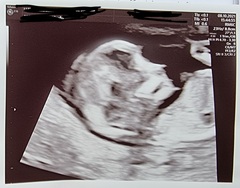

I had a scan at 7+6 and was told my due date was 15/04. I had my scan on Friday, and they adjusted it to 13+2 when I would have been 13. Due date is now 13/04 🥰🥰

Anyone else with the same due date?

Also any guesses on what my little bean is 💖💙

April 2022 Birth Club